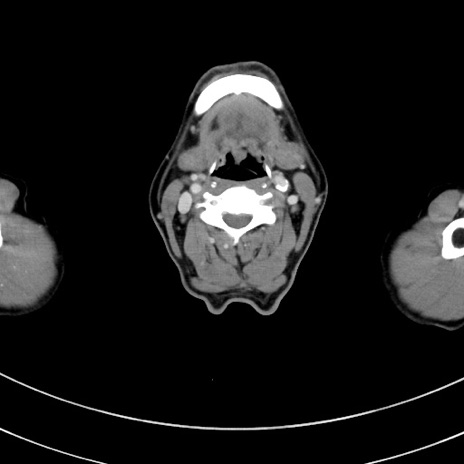

冠状断像

【症例】 60歳代男性

【主訴】 黒色吐物

【現病歴】 4日前から嘔気自覚、2日前の朝食後にも嘔気あり、自分で手で嘔吐反射起こし嘔吐したところ血が混ざっていたため受診。

【既往歴】 5年前汎発性腹膜炎を伴う急性虫垂炎で手術、高血圧、前立腺肥大症、高脂血症

【身体所見】 腹部正中に手術癩痕あり 腹部平坦・軟圧痛なし膨満感あり

【データ】WBC 8400、CRP 4.54